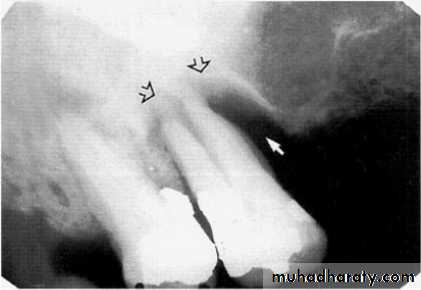

2.Vertical bone loss:- when there is greater bone loss in one tooth than on the adjacent tooth, so the bone level is not parallel with a line joining the CEJ.

Detection of Periodontal Disease

Vertical osseous defects can be divided into two primary types: Interproximal crater is a two-walled, trough like depression

that forms in the crest of the interdental bone between adjacent teeth.

The Infrabony defect is a vertical deformity within bone that extends apically along the root from the alveolar crest.